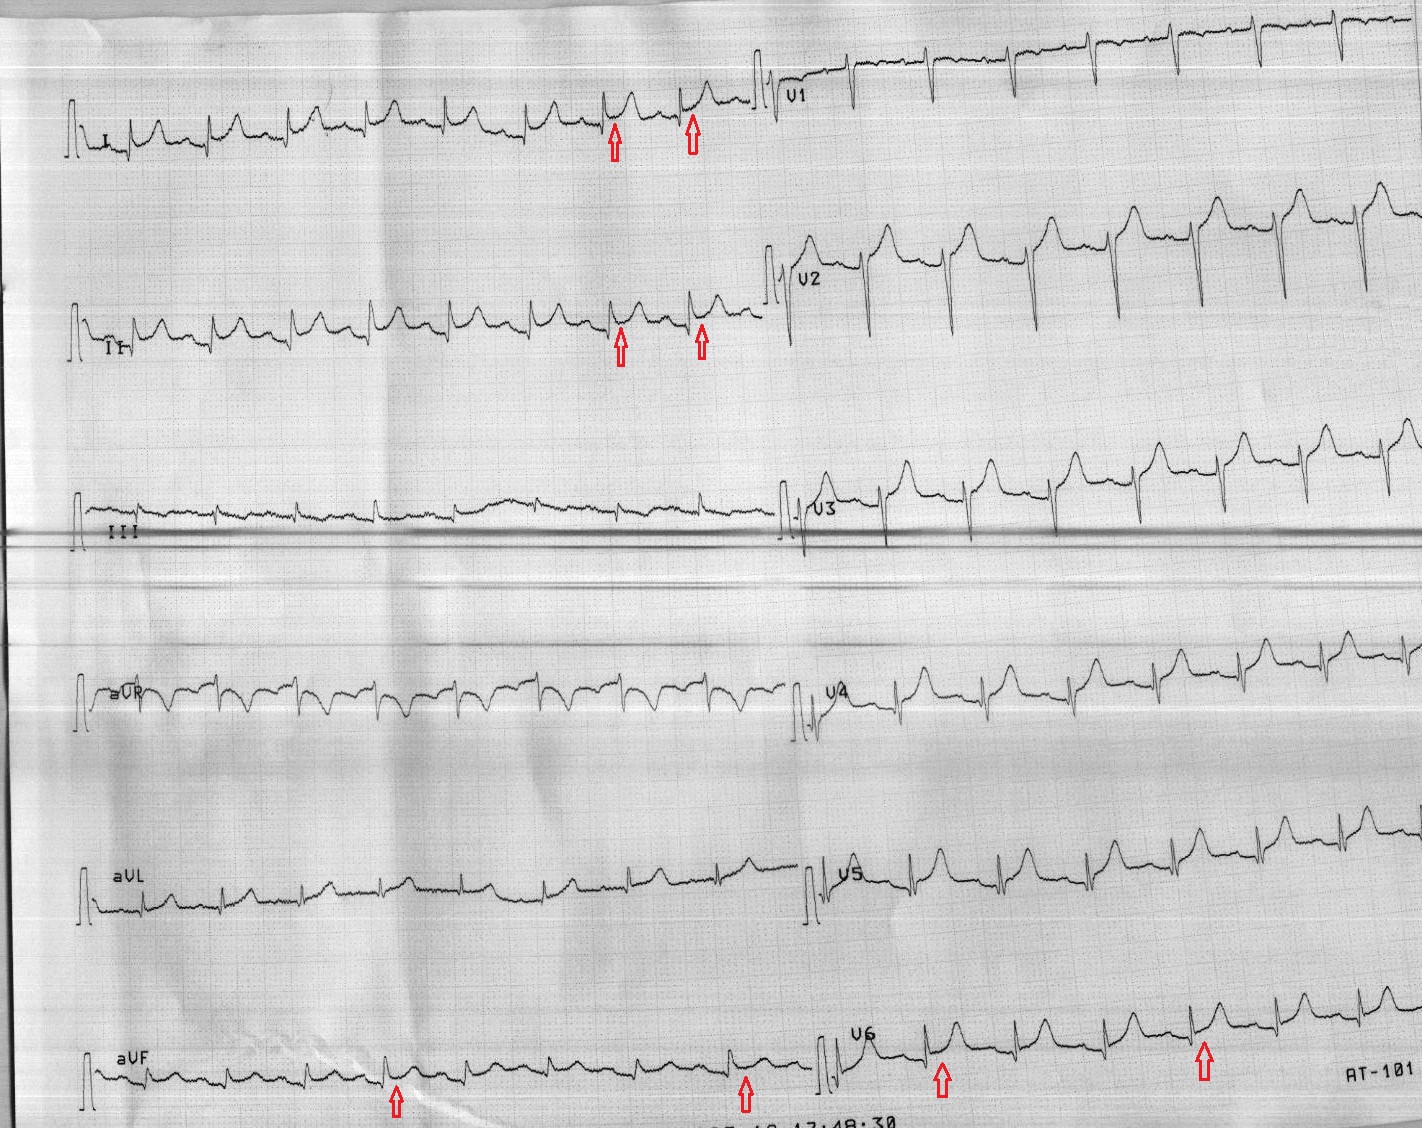

ECG recorded during chest pain. Download Scientific Diagram Chest Pain Ekg Normal Chest pain means more than pain in the chest. Chest pain should be considered acute when it is new onset or involves a change in pattern, intensity, or duration compared with previous episodes in a patient with recurrent. Learn history taking, physical examination, ecg changes and lab tests. Subtle ecg findings that may indicate acute vessel occlusion: 1 reason for. Chest Pain Ekg Normal.

ECG Review A 43YearOld Man with Atypical Chest Pain… Relias Media Chest Pain Ekg Normal Pain, pressure, tightness, or discomfort in the chest, shoulders, arms, neck, back, upper abdomen, or. Some of the first tests a health care provider may order when diagnosing the cause of chest pain include:. Typical chest pain or angina is a deep, poorly localized chest or arm discomfort (pain or pressure) associated with physical exertion or emotional stress and relieved. Chest Pain Ekg Normal.